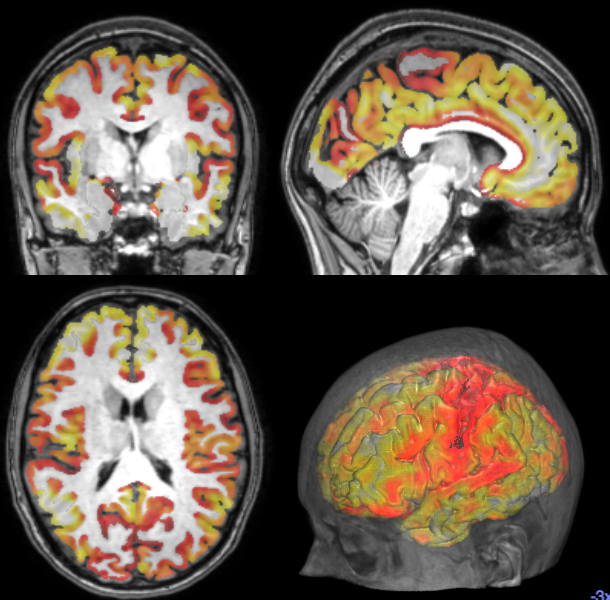

Cortical Thickness Estimation

Pipelining

- Cortical Thickness